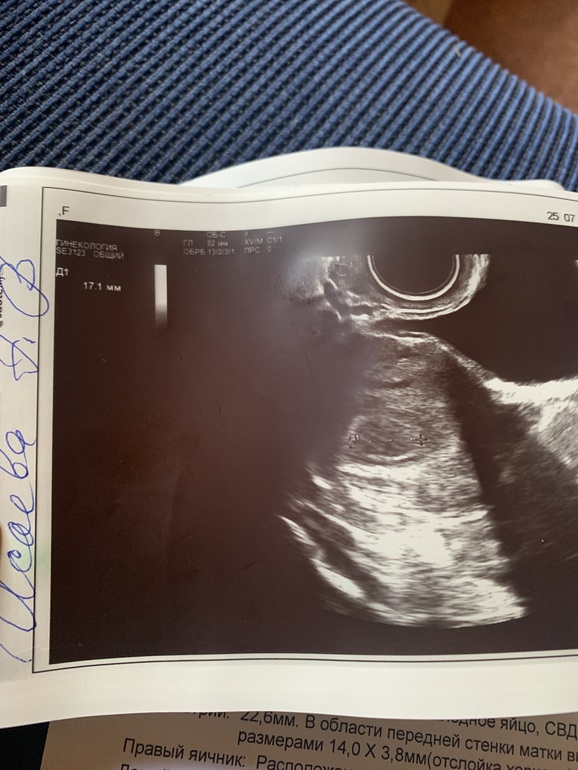

Срок по м.5+4 по узи ставят 4+2 и сдв 17.1 мм(??????) что?это ошибка или как?Может она его не так измеряла?ну не может быть такое пя.Фото прилагаю пя.Какое-то оно странное,я думала оно чёрное

Какой у вас был размер пя на +- таком дпп,ну не может же быть такое гигантское пя.Хгч 23.07 6300

Также было на 19 ДПП.На УЗИ поехала так рано из за начавшейся кровянистой мазни.СВД был 18 мм и на фото яйцо было такое же размытое.На следующий день поехала к Пятых Н.С.,там было четкое ПЯ, желточный мешочек и эмбрион с пульсацией сердечка😍. Поэтому если есть возможность, запишитесь к ней.